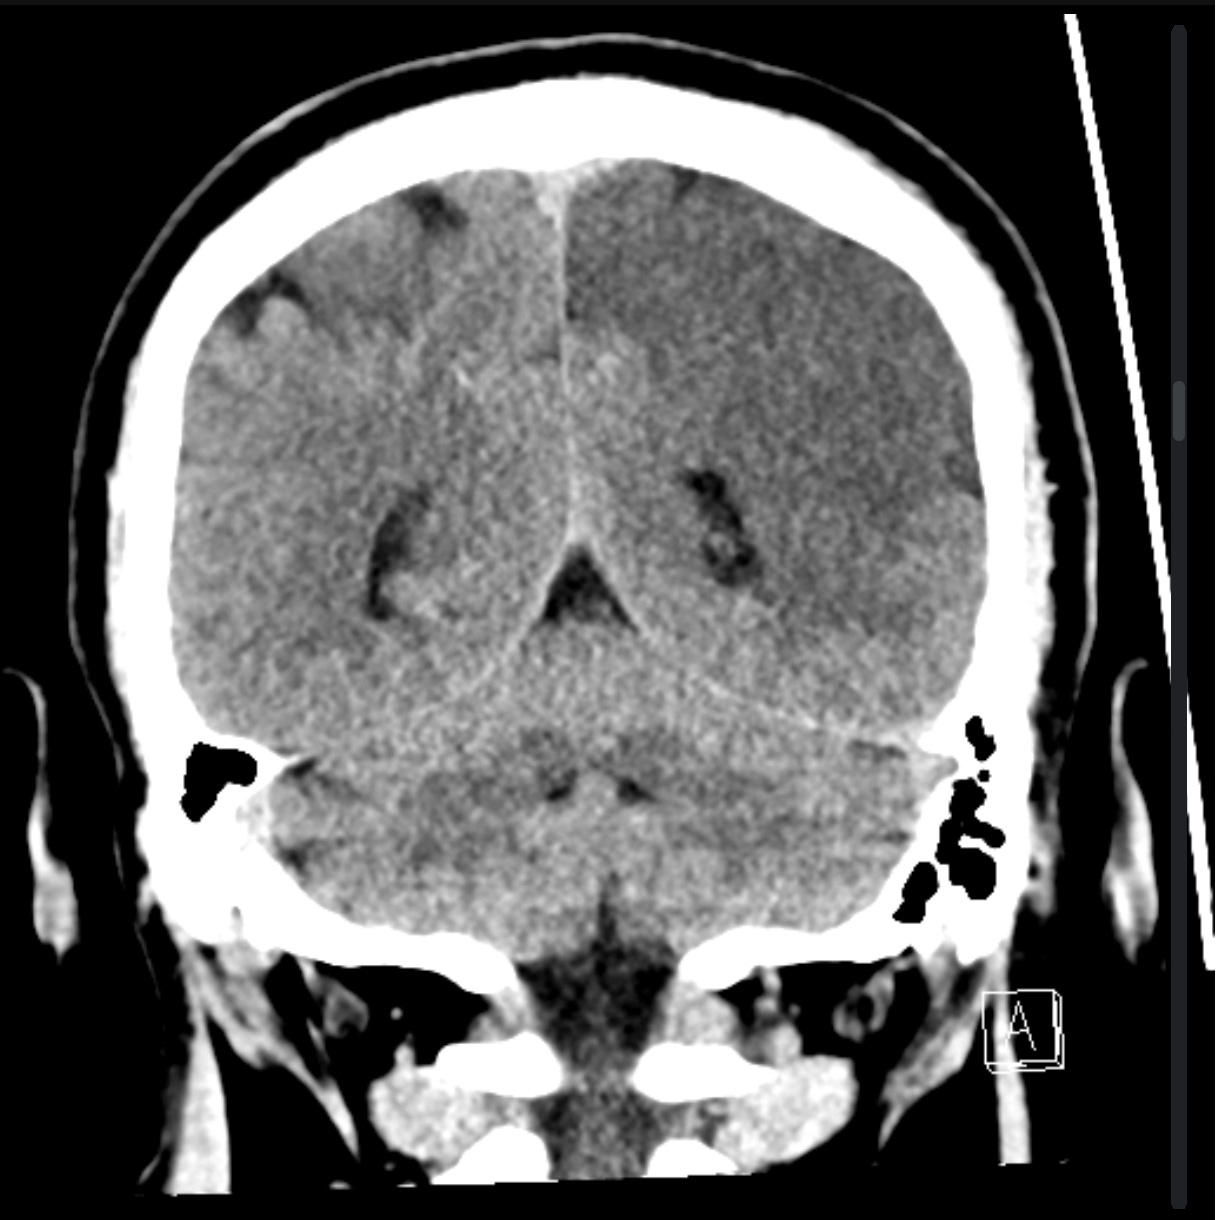

A non-contrast CT head is shown below.